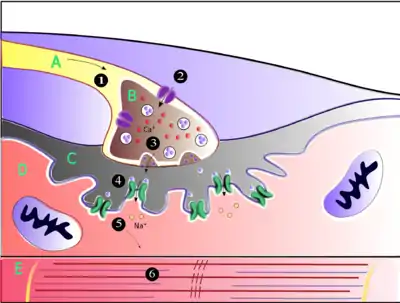

Neuromuscular junction

Acetylcholine is the substance the nervous system uses to activate skeletal muscles, a kind of striated muscle. These are the muscles used for all types of voluntary movement, in contrast to smooth muscle tissue, which is involved in a range of involuntary activities such as movement of food through the gastrointestinal tract and constriction of blood vessels. Skeletal muscles are directly controlled by motor neurons located in the spinal cord or, in a few cases, the brainstem. These motor neurons send their axons through motor nerves, from which they emerge to connect to muscle fibers at a special type of synapse called the neuromuscular junction.

When a motor neuron generates an action potential, it travels rapidly along the nerve until it reaches the neuromuscular junction, where it initiates an electrochemical process that causes acetylcholine to be released into the space between the presynaptic terminal and the muscle fiber. The acetylcholine molecules then bind to nicotinic ion-channel receptors on the muscle cell membrane, causing the ion channels to open. Sodium ions then flow into the muscle cell, initiating a sequence of steps that finally produce muscle contraction.

Factors that decrease release of acetylcholine (and thereby affecting P-type calcium channels):[11]

- Antibiotics (clindamycin, polymyxin)

- Magnesium: antagonizes P-type calcium channels

- Hypocalcemia

- Anticonvulsants

- Diuretics (furosemide)

- Eaton-Lambert syndrome: inhibits P-type calcium channels

- Myasthenia gravis

- Botulinum toxin: inhibits SNARE proteins

Calcium channel blockers (nifedipine, diltiazem) do not affect P-channels. These drugs affect L-type calcium channels.